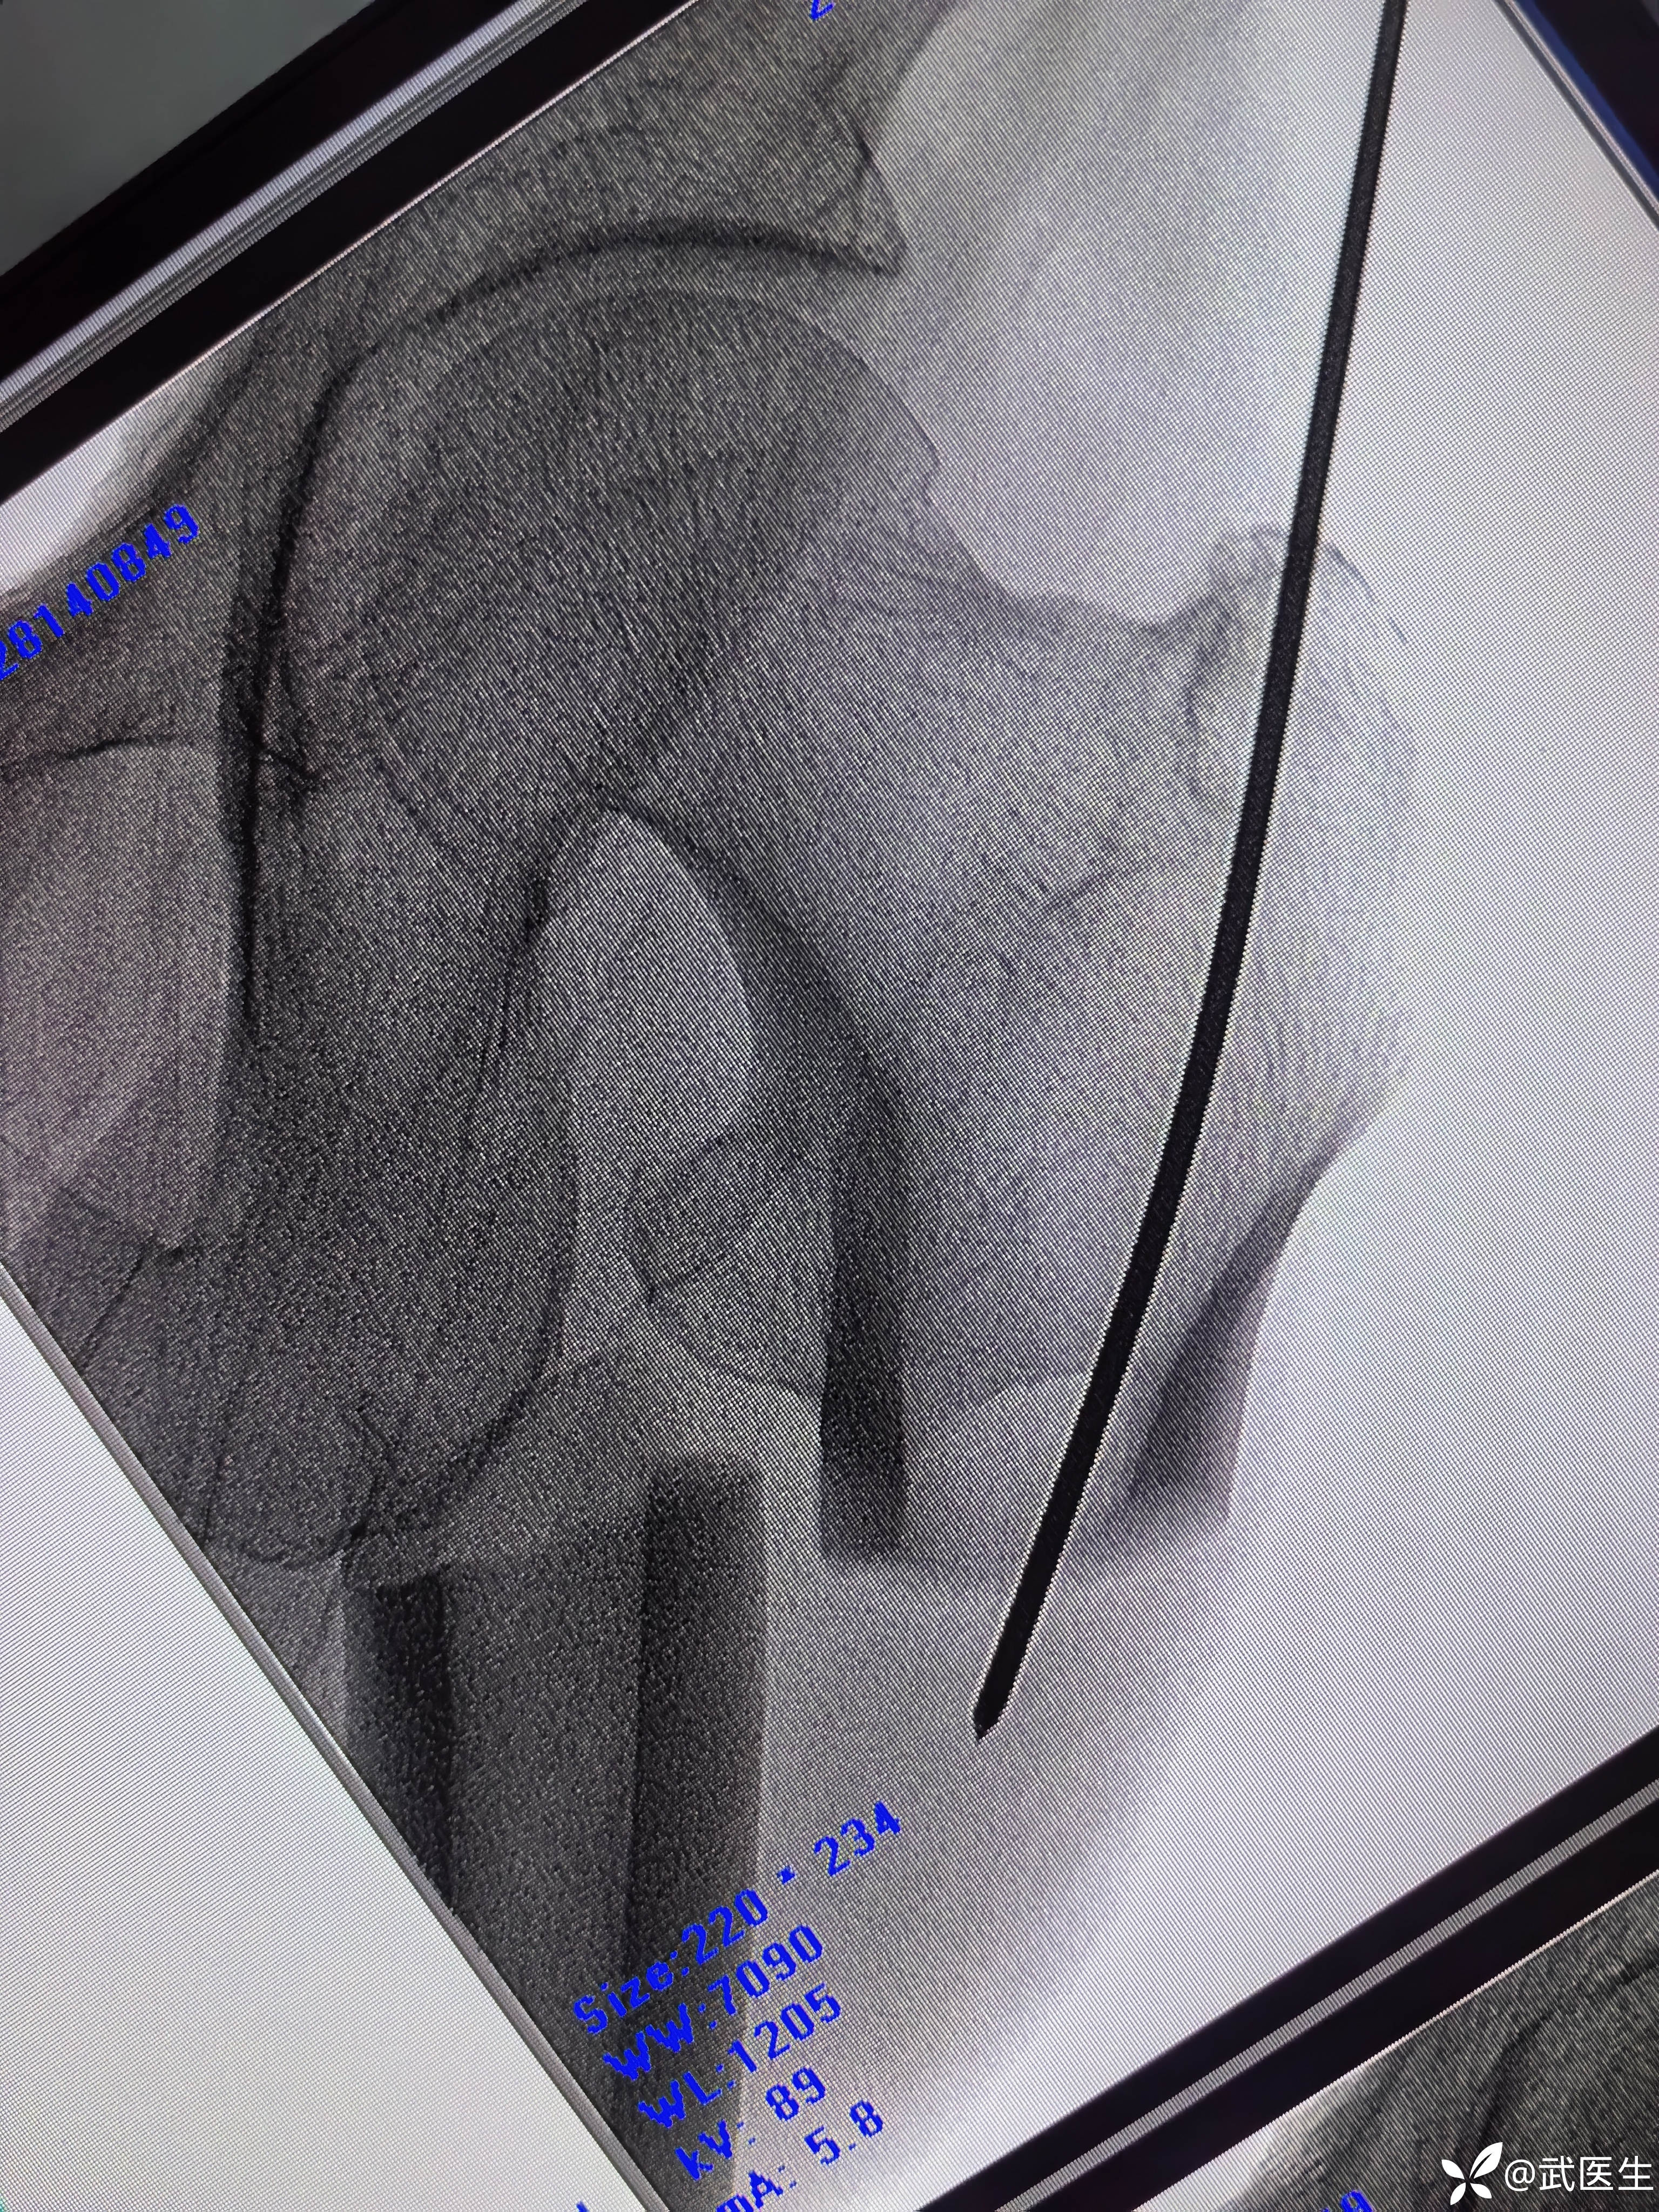

常规侧卧位,定位

合适入针点,开口,对位差,手法复位

侧位前方出现蝶形骨块

髓内钉已经很深了,头钉有点偏上,不再更换短钉了

阻挡克氏针更换为阻挡钉

最终

头钉有点偏上,髓内钉也算顶天立地。